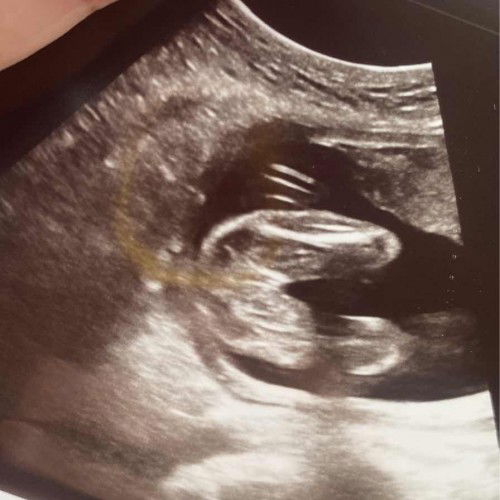

BOY OR GIRL

Nak tanya ni confirm ke girl eh? doc kata burger sign. tp risau lak saya kena scam 😅